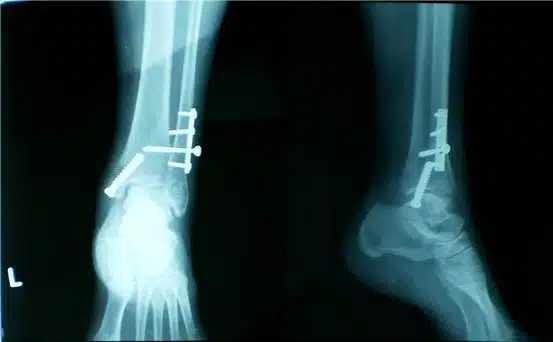

- الأشعة السينية: يخضع المريض في العادة إلى أشعة (x- ray) من أجل تحديد الصورة الهيكلية للعظم والتي مع سوء الالتئام قد تظهر في الأشعة على هيئة فراغات غير طبيعية.

- التصوير المقطعي المحوسب: يتم استخدام هذه الأشعة من أجل الحصول على تصور واضح للإصابة من الداخل من جميع الاتجاهات لتحديد المشكلة بشكل أوضح وبشكل أدق خاصة في حالة التئام الخاطئ.